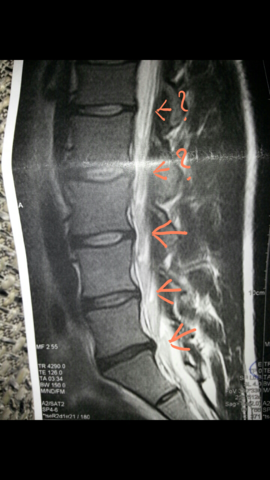

Bandscheibenprotrusion l4/5. They are relatively easy to overlook as they do not impinge upon the spinal canal. Die Bandscheibenprotrusion der LWS beschreibt nun den Zustand in dem sich einer der Kerne einer Bandscheibe nach hinten vorgewölbt hat und auf Teile des Rückenmarks oder zentrale Nerven drückt. Die Symptome ähneln dann denen eines Bandscheibenvorfalls.

They do not narrow the subarticular recess but compresses the exiting nerve root only thus clinically mimicking a posterolateral disc from the level aboveAs posterolateral discs are common as is multilevel. Computertomographisch zeigten sich ein Vakuumphänomen und eine Bandscheibenprotrusion mit Forameneinengung rechts L45 bei. Die Bandscheibenprotrusion auch Bandscheibenvorwölbung oder inkompletter Bandscheibenprolaps ist eine mit dem Alter zunehmend häufiger zu beobachtende Veränderung im Bereich der Wirbelsäule.

These levels were investigated in this study as degeneration occurs most often and earliest in these three lower vertebral levels 17 fourth and fifth lumbar spine vertebrae and the first sacral vertebra were evaluated for disc bulging and protrusion See Lumbar Artificial Disc Replacement for Chronic Back Pain A high intensity zone HIZ is seen at L4-L5 Depending on the extensiveness. Es wurde eine ausgeprägte Osteochondrose mit Pseudolisthese und Bandscheibenprotrusion L45 diagnostiziert. Bei einer Bandscheibenprotrusion können die Nervenwurzeln hier blau geschädigt werden.

Protrusion L4 5 Bandscheibenprotrusion L4 L5 Mrt Lws